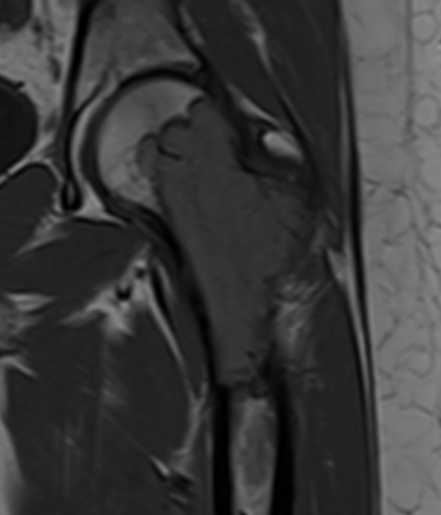

MRI

Low signal intensity T1 / high signal intensity T2

Areas of ABC seen in 10 - 14%

Look for signs of grade III: soft tissue extension